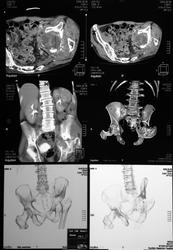

Реконструкции

Реконструкции добавлены. Остался последний рывок. Находим всё ранее ненайденное (кисту в левой почке даже я вижу).

на серии кт определяются в средней трети левой почки ,латерально от ее ворот определяется гиповаскулярный участок с четкими ровными контурами .с поддавливанием чашечно-лоханочной системы,ограниченый капсулой почки ,неправильной вытянутой формы ,который в поздней венозной фазе не изменяет своей визуализации (д.д между кистой и кистозной формой почечно-клеточного рака).латерально от левой почки в мягких тканях определяется большой участок со сниженной денситометрической плотностью,размерами - 53х117мм ,с включениями газа и кольцом периферического усиления,с дренажом(вероятнее всего крупный абсцесс).печень увеличена в размере,селезенка с включениями кальция .размеры поджелудочной железы в пределах нормы,холедох и вирсунгов проток без патологии.надпочечники нормальных размеров,без изменений.в области левого тазобедреного сустава определяется участок деструкции с разрушением вертлужной впадины ,головки и шейки бедренной кости ,смещением повздошной кости вверх и латерально на 111.1мм,с фрагментом головки левой бедренной кости .в левой повздошной кости определяются гиперостоз с обширным участком остеосклероза и мелкими участками остеолитической деструкции (смешанный тип).аналогичные остеолитические изменения в крыле правой повздошной кости и в головке правой бедренной кости (сужу по 3d).по медиальному контуру средней трети тела поздошной кости определяется разрушение замыкательной пластинки с вовлечением губчатого вещества на большом протяжении,в крыше и самой вертлужной впадине с мягкотканным компонентом ,с участками пониженной денситометричской плотности (вероятнее всего участки некроза),с мелкими костными фрагментами (что косвенно может подтверждать рост изнутри снаружу),с поддавливанием на большом протяжении органов малого таза,латерально -левая стенка мочевого пузыря утолщена.вывод :такие изменения могут быть как первичного так и метастатического характера .первопричина протрузии возможно врожденного характера(дисплазия) ,затем перелом усугубил процесс(посттравматическая протрузия).меня настораживает тот момент,что изменения в повздошной кости напоминают хронический остемиелит изначально .а затем появились изменения ,сильно напоминающие озлакочествление+изолированно крупный абсцесс

5. Деструкции справа не вижу. Оценивать её по 3D считаю некорректным.